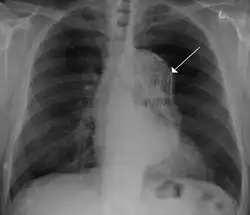

Contrast enhanced CT of a ruptured large (7 cm) thoracic aneurysm, with black arrow indicating the aorta, and white arrow blood in the thorax